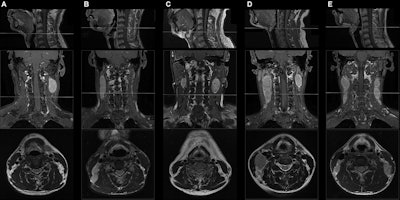

Sagittal T1-weighted fat-suppressed contrast-enhanced MRI scans (top row) show the caudal border of the hyoid bone. Coronal T1-weighted fat-suppressed contrast-enhanced (middle row) and axial T2-weighted MRI scans (bottom row) show the presence or absence of middle neck involvement in five patients with N1 or N2 nasopharyngeal carcinoma (NPC). (A) A 49-year-old male patient with N1 NPC and without middle neck involvement. (B) A 45-year-old male patient with N1 NPC and middle neck involvement. (C) A 49-year-old male patient with N2 NPC and without middle neck involvement. (D) A 30-year-old female patient with N2 NPC and unilateral middle neck involvement. (E) A 19-year-old male patient with N2 NPC and bilateral middle neck involvement. Images and caption courtesy of the RSNA.